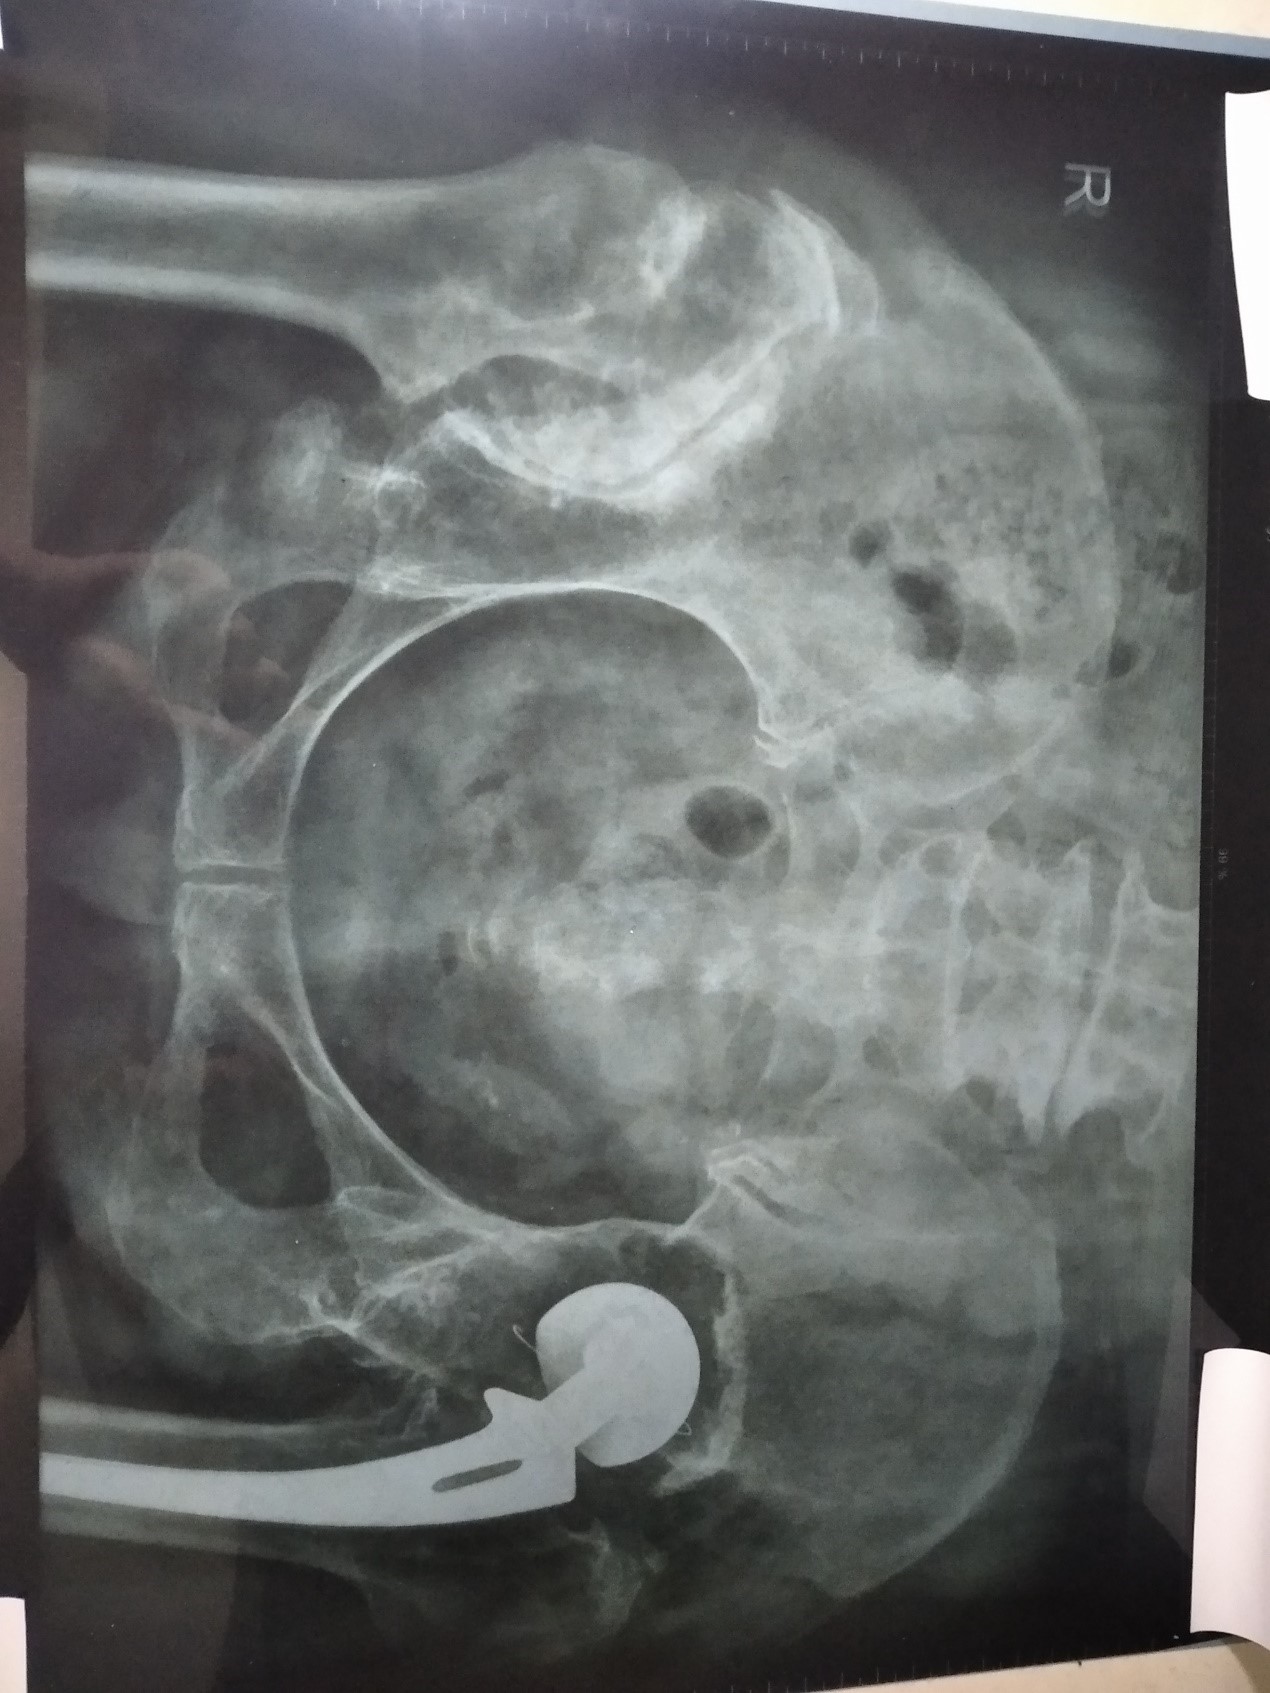

今年三月二十一日到医院拍了一个片子,我把DX影像诊断报告单抄写如下:

检查项目:骨盆IR:骨盆(正位)

影像表现:显示右髋关节髋臼变浅,密度增高,股骨头上移位,形成假关节,股骨头扁平宽大,密度增高。左髋关节人工关节置换术后,余各骨质结构良好,骨小梁清晰,关节间隙正常,关节面光整。

通过片子看,右侧髋关节是形成了假关节,所以我右侧的髋关节脱位的问题解决了。而且活动范围扩大,持重力增强,整个腿也归正了,身体也直了。我整个身体以前是向右侧弯曲的,所以左侧髋关节也向外突出。现在右腿恢复了以后,身体变直了,左侧关节也進去了,而且膝关节也逐渐的消肿、变直,整个左腿正常健康了。